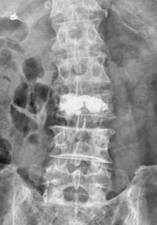

椎体形成術(VP、BKP、VBS)および後方・後側方脊椎固定術

対象となる疾患:脊椎圧迫骨折や転移性脊椎腫瘍による病的骨折など

椎体形成術でセメントや人工骨を注入して、骨折を人工的に接合します。椎体形成術のみでは固定性が弱い場合や骨脆弱性が強い場合には、スクリューなどを用いて脊椎を安定化させます。原則、手術翌日より軟性もしくは硬性のコルセットを装着し、起立・歩行を開始します。

(左)第12胸椎および第1腰椎の骨粗鬆症性椎体骨折を認めます。(中)MRIでは第1腰椎に大きな骨欠損を認め、骨折が難治性で不安定であることを示しています。(右)第1腰椎に椎体形成術を施行し、さらに骨が脆かったため、頭尾側にスクリューを挿入して固定しています。